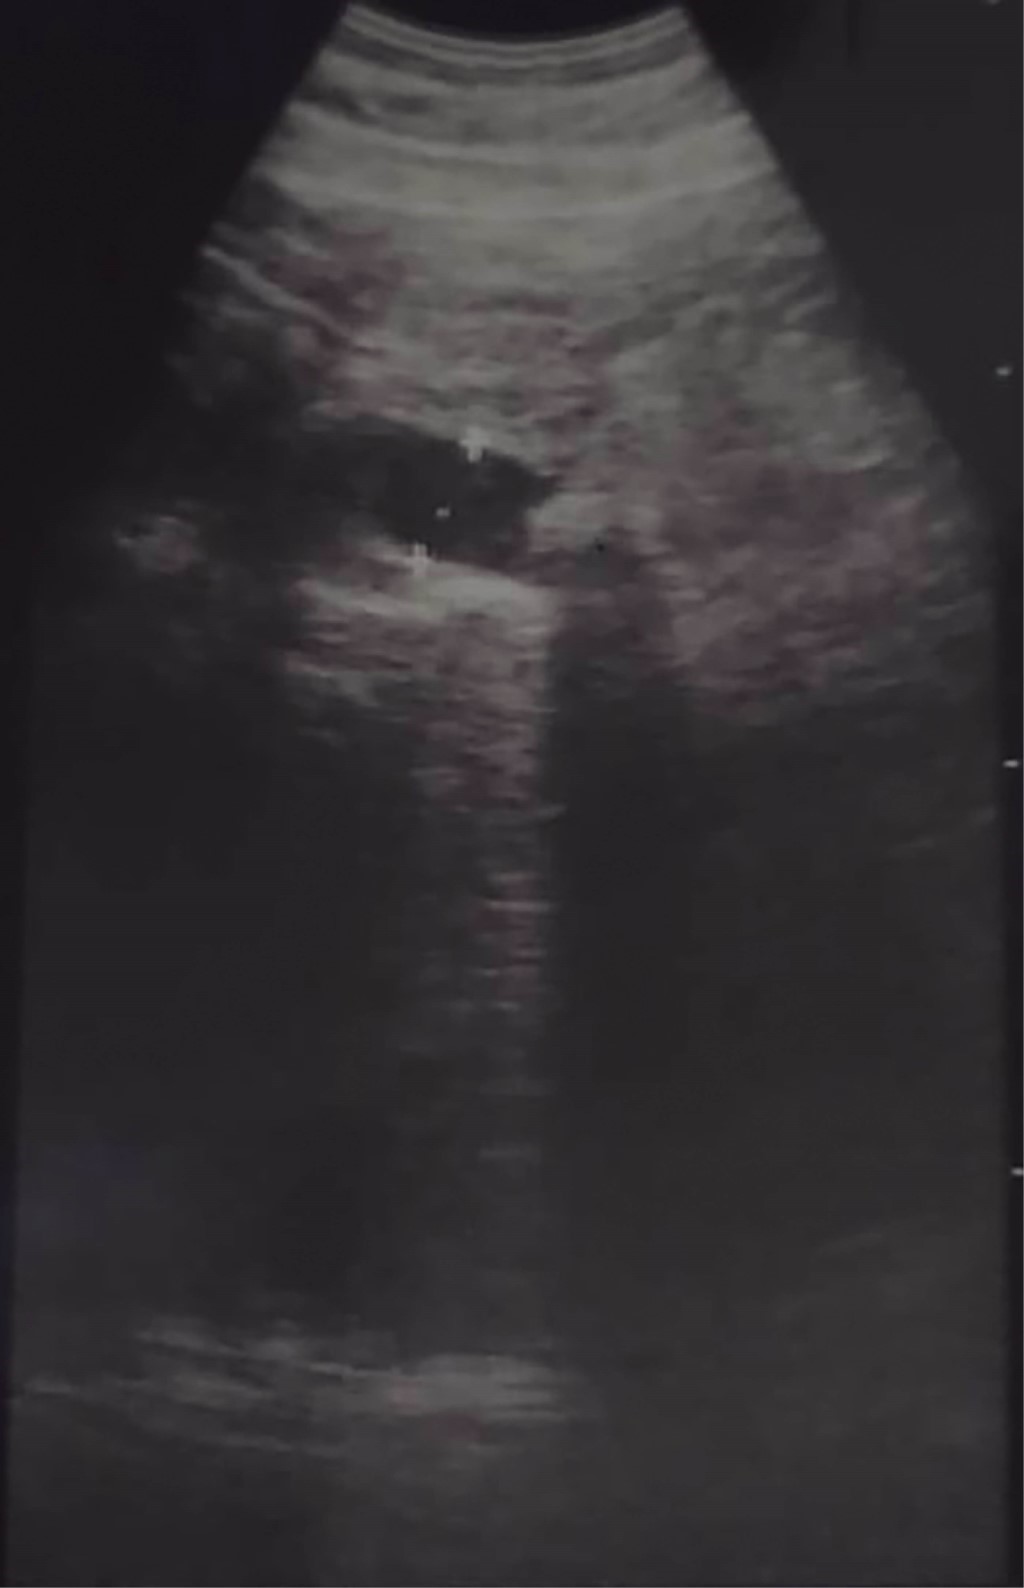

Masculino de 64 años, quien inicia su padecimiento con ictericia, negando otra sintomatología, llama la atención que se manifesta durante al menos tres días previos a su llegada a urgencias, su exploración física sin alteraciones, los laboratorios revelan una bilirrubina total de 25 mg/dl, bilirrubina directa de 22 mg/dl, fosfatasa alcalina 235 UI/l, gamma-glutamil transferasa 157 UI/l, creatinina 2.5 mg/dl, el resto de los laboratorios normales, se le realiza un ultrasonido de abdomen que reporta vesícula biliar mal definida, y dilatación de la vía biliar de 19 mm (Figura 1), se observa lito en colédoco de alrededor de 12 mm. Se integra el diagnóstico de coledocolitiasis, no obstante, se solicitan marcadores tumorales, con reporte de CA 19-9 de +8,000 UI; se solicita colangiorresonancia, la cual evidencia dilatación de vía biliar (vb) de 20 mm, lito de 16 mm a nivel del ámpula, no se reporta morfología de la vesícula biliar (VB), paciente candidato a colangiopancreatografía retrógrada endoscópica (CPRE) según el servicio de Gastroenterología. Se le realiza CPRE sin poder extraer lito, se programa para colecistectomía con exploración de vía biliar, el transoperatorio revela biliperitoneo, lisis de VB, fístula colecistocoledociana (Figura 2), litio único de 15 mm, se coloca sonda T, no se cuenta con servicio de cirugía hepatopancreatobiliar, por lo que no se realiza reparación definitiva, colangiografía transoperatoria revela paso de material de contraste a duodeno, sin fugas aparentes por orificio fistuloso (Figura 3), evolución posoperatoria favorable, el drenaje por sonda T en promedio 500 ml por día con disminución progresiva, con mejoría de hiperazoemia, con flujo urinario mayor a 0.5 ml/kg/h, colangiografía posoperatoria sin fugas, paso de medio de contraste a duodeno, reporte de patología revela adenocarcinoma de vesícula moderadamente diferenciado con infiltración a muscular (Figura 4). El paciente rechaza tratamiento médico y decide egreso voluntario, comprende y acepta los riesgos, no contamos con seguimiento a largo plazo.

Por otro lado, el CAVB es el cáncer más frecuente de la vía biliar, 80% con respecto al colangiocarcinoma, se encuentra de manera más común en fundus (60%), cuerpo (30%) y cuello (10%), el tipo histológico más frecuente es el adenocarcinoma, se considera invasor al sobrepasar la muscularis propia, es decir, los estadios T1a (Figura 4); es frecuente encontrar casos con perforación del peritoneo visceral e invasión a órganos adyacentes, sin embargo, el diagnóstico intraoperatorio y tratamiento radical sólo se realiza en menos de 1% de los casos.8-10

Figura 4